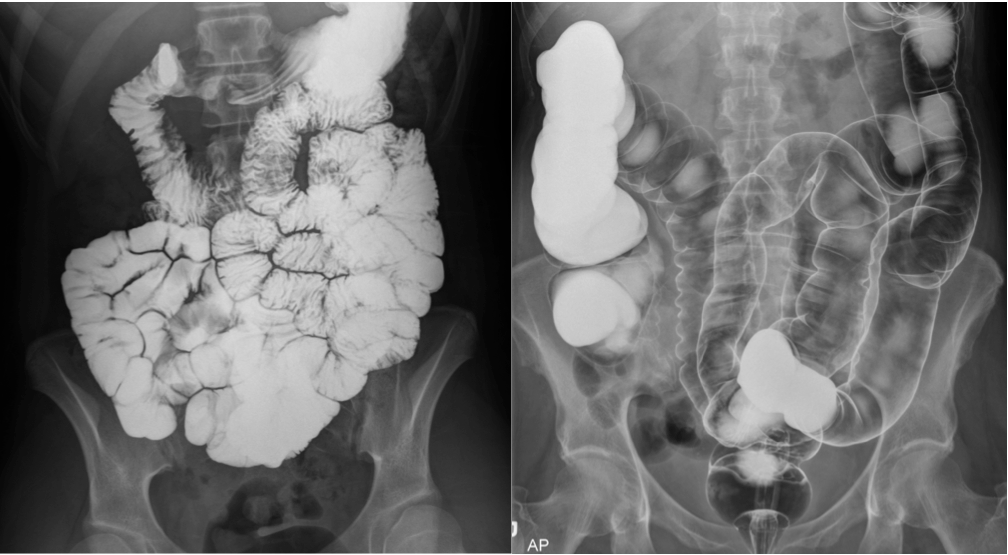

What are the indications for obtaining a fluoroscopy?

What contrasts are employed?

Pain, dysphagia, diarrhea, hernias, colon cancer

Double contrast-air and barium - mucosal detail

Single contrast-barium only - peristalsis, wall, folds, caliber